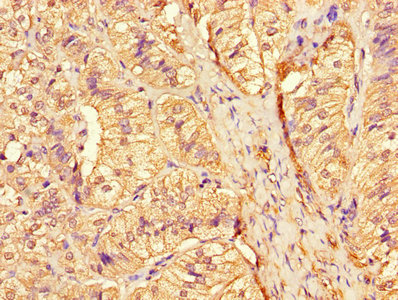

Immunohistochemistry of paraffin-embedded human adrenal gland tissue using CSB-PA006184LA01HU at dilution of 1:100